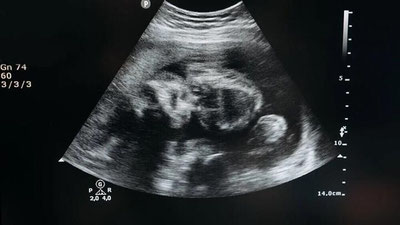

Как было отмечено, в последние годы в нашей стране проводится большая работа по охране здоровья детей, укреплению репродуктивного здоровья населения, а также приближению первичной медицинской помощи к населению.

В первичном звене внедрены программы профилактики, раннего выявления и оздоровления среди матерей и детей, и благодаря совершенствованию специализированной медицинской помощи в этом направлении, уровень материнской смертности снизился на 34%, а смертность детей до пяти лет — на 26%.

В масштабах республики, в регионах и районах (городах) на системной основе налажены работы по контролю, анализу, выявлению и устранению недостатков в оказании помощи матерям и детям на принципе «365 дней/24 часа».